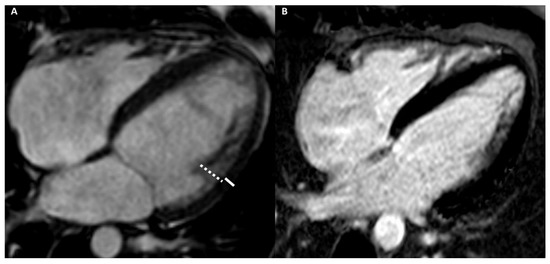

2.6. Late Gadolinium Enhancement

2.7. Stress Imaging

| LGE/LIE | |||||||

| Type | Linear | Patchy or massive | Linear | Linear | Linear | Linear | Linear or parchy |

| Layer | Mesocardial | Mesocardial | Mesocardial | Mesocardial | Subepicardial Mesocardial | Subepicardial | Subendocardial Mesocardial |

| Site | Interventricular juctions | Hypertrophic area; interventricular junctions | Septum; infero-lateral LV wall | Variable, not associated with NC area | Anterior RV wall | Infero-lateral LV wall | Circumferential; septum; lateral LV wall |